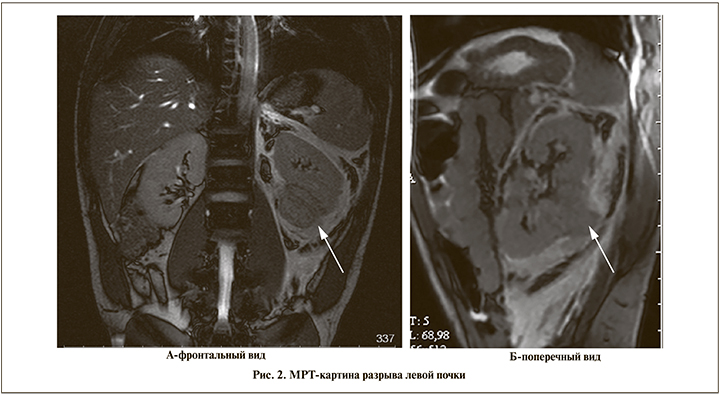

Пострадавший О. 1984 г.р. Травму получил при ДТП. Через 4 ч отметил примесь крови в моче. В урологическом отделении районной больницы при УЗИ заподозрен разрыв паренхимы левой почки. Однако при внутривенной урографии данных за нарушение функций обеих почек не получено. Оперативное лечение не предлагалось. Переведен в 3ЦВКГ им. Вишневского на следующие сутки. При МРТ: левая почка деформирована с нечеткостью контуров; на уровне среднего и нижнего сегментов по задней поверхности определяется выбухание бесформенного участка паренхимы за пределы контура почки; кортико-медуллярная дифференциация сглажена. Паранефральная клетчатка слева на значительном протяжении инфильтрирована и имбибирована кровью, инфильтрация распространяется по ходу почечной ножки (рис. 2). Правая почка без патологических изменений.

Решение консилиума врачей: показано под эндотрахеальной анестезией (ЭТА) экстренная операция в объеме люмботомии, ревизии забрюшинного пространства. Интраоперационно диагностирован разрыв паренхимы нижнего полюса почки, идущий через нижние группы чашек с повреждением лоханки. Выполнена резекция нижнего полюса левой почки, установлена нефропиелоуретеростома (рис. 3). Под рентгенологическим контролем дренаж удален на 4-е сутки, уретральный катетер и швы с полеоперационной раны – на 10-е сутки. Нефростомический дренаж удален на 45-е сутки. При внутривенной и антеградной урографиях через 4 дня после операции затеков контрастного вещества за пределы почки нет.